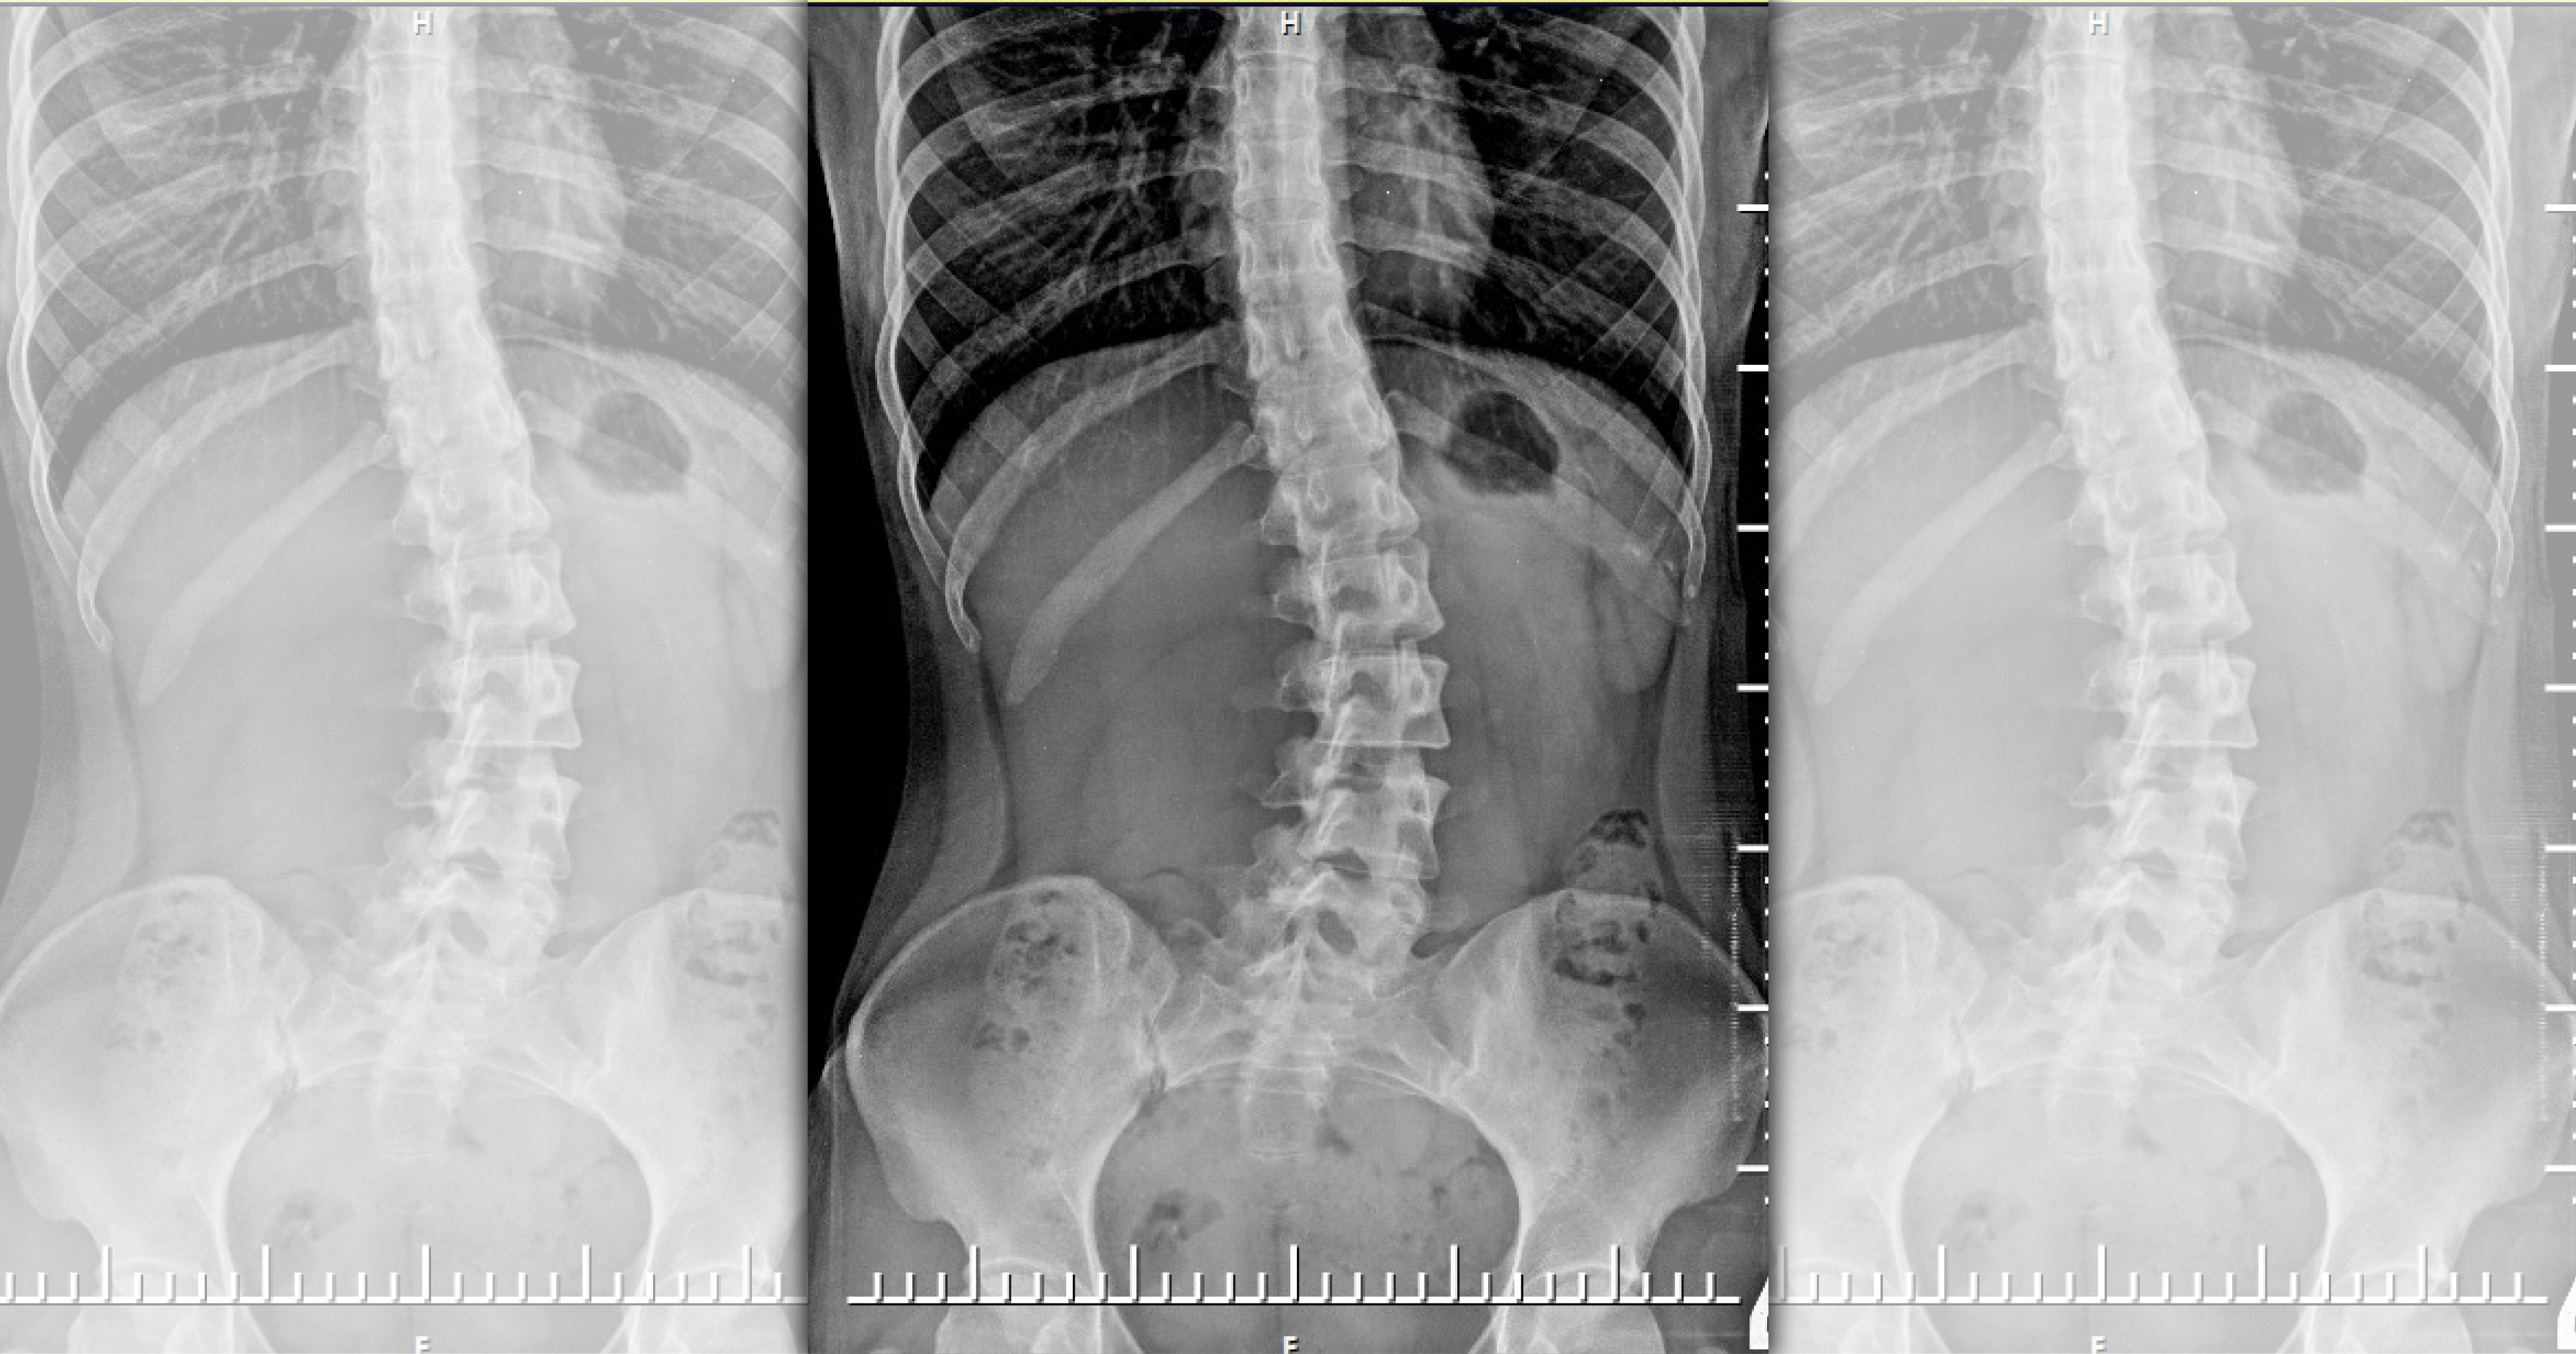

綜合媒體報導,該名學生的脊椎側彎歪斜角度在3個月內從30度暴增至45度,甚至出現胸悶狀況,原來是家長自行上網找尋偏方導致快速惡化,讓家長相當後悔。通常側彎角度超過40度,就需要開刀治療,但醫師考量該名學生年紀還小,應可先嘗試使用背架矯正,經過半年的時間調整,該名學生的側彎度數明顯獲得改善,暫時不需要手術,但仍需穿戴背架至18歲、發育成長期結束為止。

報導指出,台灣脊椎側彎的發生率約占2%至5%,好發於青少年時期,嚴重者可能壓迫到臟器,影響心肺、消化功能,目前醫學尚未有確切病因。脊椎側彎角度介於20度至40度的患者,需要積極穿戴矯正背架,並配合密集門診追蹤、專業的側彎運動;40度以上者則需要以手術治療。